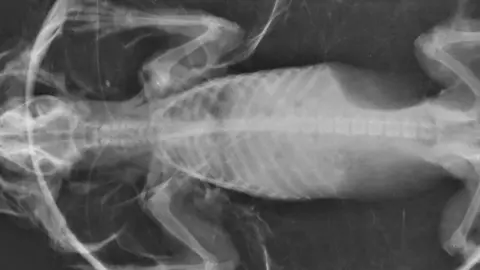

"Zeppelin suffered from 'balloon syndrome'. It's likely that he was clipped by a car, puncturing a lung and causing air to become trapped under his skin.

"He's certainly one of the largest hedgehogs we've taken into our care, with a circumference of 30 inches."

Mr Seddon added: "Zeppelin had a difficult time recovering, the hole we made in his skin kept healing faster than his punctured lung, we had to put plastic in with his spines to ensure the excess air could escape as the poor guy kept re-inflating."